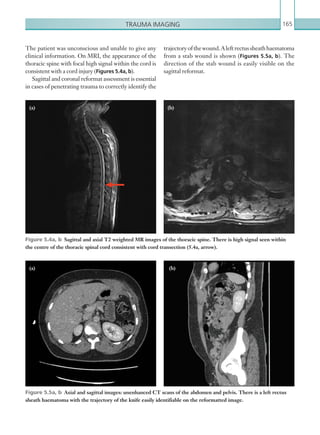

• 80.

Chapter 258 Radiological findings Computedtomography The presence of extraluminal oral contrast in the posterior mediastinum (which can also track into the left-sided pleural cavity) is indicative of oesophageal perforation (Figures 2.48, 2.49). An additional helpful signispneumomediastinum;utilisationoflungwindow settings aids visualisation of this (Figure 2.50). It should be noted that this is a non-specific sign and if seen in isolation, additional causes should be considered (Table 2.15). Concentric or eccentric oesophageal muralthickeningcanalsobeseenincasesofoesophageal perforation, although it is also non-specific and can be seen with oesophagitis or malignancy; the presence of associated para-oesophageal lymphadenopathy is more suggestive of the latter. Para-oesophageal enhancing fluid collections may also be seen. Note: Small oesophageal leaks may be missed on CT, especially in the absence of oral contrast; this should be emphasised in the report. Fluoroscopy Contrast swallow fluoroscopy should be performed with the patient in a semi-supine (20°) position, right Figure 2.48  Axial image: oral and IV contrast enhanced CT scan of the thorax in the arterial phase. Oral contrast is seen collecting in the right pleural space with locules of gas. Left pleural effusion is also noted. Figure 2.49  Axial image: oral contrast CT scan of the thorax. Contrast can be seen within the stomach. Contrast has collected around the oesophagus within the posterior mediastinum (arrow). A left-sided pleural effusion is also present, containing locules of gas. Figure 2.50  Axial image: IV contrast enhanced CT scan of the thorax in the arterial phase. Viewed on lung window settings, gas can be seen surrounding the ­superior mediastinal structures. andleftanterioroblique,rightandleftlateralandprone positions, although this depends on patient tolerance. Ideally, the patient should swallow the oral contrast mediumfromacupondemand.Bolusesoforalcontrast K22247_C002.indd 58 16/05/15 3:07 AM

• 81.

Gastrointestinal and genitourinaryimaging 59 • Blunt chest trauma. • Secondary to chest, neck or retroperitoneal surgery. • Oesophageal perforation. • Tracheobronchial perforation. • Vigorous exercise. • Asthma. • Barotrauma. • Subcutaneous emphysema, pulmonary interstitial emphysema. • Stab wound. • Infection. • Idiopathic. Table 2.15  Causes of pneumostinum. Figure 2.51  PA chest radiograph. Streaky linear ­lucencies are seen within the superior mediastinum and outlining the left heart border. Subcutaneous ­emphysema is also seen in the supraclavicular fossa bilaterally. Reference Tonolini M, Bianco R (2013) Spontaneous esophageal perforation (Boerhaave syndrome): diagnosis with CT-esophagography. J Emerg Trauma Shock 6:58–60. should be followed down the entire oesophagus. Rupture is confirmed in the presence of extravasation of oral contrast or an irregular collection of contrast external to the oesophageal lumen. Additional findings include oesophageal wall irregularity and distortion, which may suggest para-oesophageal collections. Adequate oesophageal luminal distension is vital to identify oesophageal perforation; this requires a good oral contrast load. The study should always be terminated if oral contrast material is aspirated. Plain films Chest plain film findings are all non-specific but can suggest the diagnosis of oesophageal perforation. The most common sign of oesophageal perforation seen on chest plain film imaging is a left-sided pleural effusion and atelectasis/consolidation, reflecting the fact that the most common site of oesophageal perforation is the distal left-sided posterior wall. Pneumomediastinum should always raise suspicion of oesophageal perforation, especially in the presence of associated symptoms. Pneumomediastinum has many appearances on chest plain film imaging, although all rely on the presence of abnormal gas outlining the normal mediastinal structures (Figure 2.51). Note: Pneumomediastinum on plain film imaging has a low sensitivity and specificity for oesophageal rupture and can be seen in many other conditions (Table 2.15). Key points • Oesophageal perforation has a high mortality rate and urgent diagnosis is essential. • Imaging modalities include CT with water soluble oral contrast and fluoroscopy. Small leaks can be missed on both modalities if the oral contrast load is inadequate. Report checklist • Presence or absence of extra-oesophageal oral contrast. • Attempt to localise any potential oesophageal breach. • Document any associated complications (e.g. mediastinal collections and mediastinitis). K22247_C002.indd 59 16/05/15 3:07 AM

• 82.

Chapter 260 and non-compression)is most diagnostic in the hands of experienced sonographers and radiologists. In the on-call setting, the use of ultrasound and experience in scanning for appendicitis may be limited. (See Table 2.16.) Radiological findings Computed tomography The appendix should be identified – the use of multiplanar reformatting is sometimes necessary to achieve this. The normal appendix appears as a tubular or ring-like pericaecal structure that is either totally collapsed or partially filled with fluid, contrast material or air. It has a thickness less than 3 mm. Acute appendicitis causes thickening of the appendix with a two-wall diameter greater than 6–7 mm. Periappendicular inflammatory stranding and free fluid may also be seen (Figure 2.52), as may a calcified appendicolith (seen in 30% of cases, Figure 2.53). Other conditions, such as active Crohn’s disease in the terminal ileum, can cause a similar appearance of a thickened tubular structure in the right iliac fossa. It is important to differentiate the two structures anatomically, since the management of the two conditions differs. Caecal thickening and inflammatory changes may be present, and if oral contrast has been given, it may give rise to an ‘arrowhead’ appearance, as contrast funnels at the caecal apex to the point of the obstructed appendicular orifice. Perforated appendicitis is usually accompanied by pericaecal abscess formation, which presents as an enhancing fluid collection (Figure 2.54). These may ACUTE APPENDICITIS Acute appendicitis is the most common cause of acute abdominal pain and is a surgical emergency. Appendicitis occurs in all age groups; it is rare in infants but becomes increasingly common in childhood, reaching peak incidence in the late teenage years and early twenties. Abdominal pain is the primary symptom of appendicitis and is initially located in the lower epigastrium or periumbilical area. The pain subsequently localises to the right lower quadrant, where it becomes progressively more severe. Anorexia nervosa nearly always accompanies appendicitis. Nausea, vomiting and low-grade fever are common symptoms. Less commonly, diarrhoea or constipation may be seen. The physical examination findings in acute appendicitis are localised abdominal tenderness, rigidity, muscle guarding, pain on percussion and rebound tenderness. Pain in the right lower quadrant with palpation of the left lower quadrant (Rovsing sign) is helpful in supporting a clinical diagnosis. High C-reactive protein (0.8 mg/dl) with leucocytosis and neutrophilia is the most significant laboratory finding. The diagnosis of acute appendicitis is primarily a clinical one; however, many conditions have similar clinical presentations to appendicitis and a definitive diagnosis may be difficult to make. In these cases of clinical uncertainty, the on-call radiologist may be required to aid the diagnosis. Radiological investigations Both CT and ultrasound can be useful in the diagnosis of acute appendicitis and its complications. Radiology, primarily CT, can reduce the number of misdiagnoses and negative laparotomies, with high positive and negative predictive values of between 95 and 98% and 95 and 100%, respectively (Curtin et al., 1995). In addition,itcanbeofuseinthedetectionofappendicular abscesses, postoperative complications and other conditionsmimickingappendicitis.Ultrasoundalsohas a diagnostic role in patients where CT is less favourable (e.g. children, young women and pregnant women). The reported positive and negative predictive values are 91 to 94% and 89 to 97%, respectively (Curtin et al., 1995). The use of ultrasound (compression MODALITY PROTOCOL CT Post IV contrast, portal venous phase: 100 ml IV contrast, 4 ml/sec via 18G cannula. Scan at 70 seconds. Scan from above diaphragm to femoral head level. Ultrasound 6–9MHz linear probe. Table 2.16 Acute appendicitis. Imaging ­protocol. K22247_C002.indd 60 16/05/15 3:07 AM